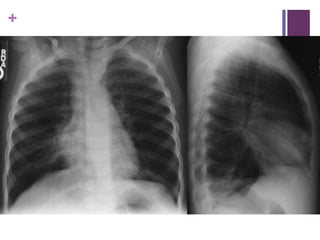

Case 4

 2 yo F with SOB/fevers/cough/grunting for 5/7

 Pneumonia

+